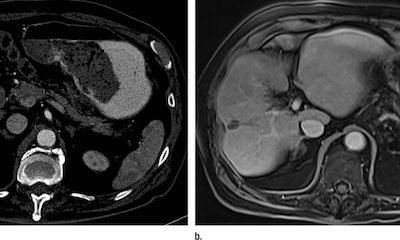

海外醫(yī)療:新型分段式放療成為肝癌治療新方法